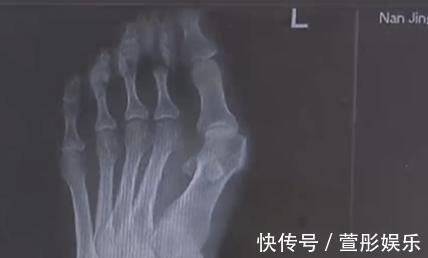

【 拇指 爱穿高跟鞋的女性一定要小心,拇指外翻堪比“裹脚”!不可忽视】如今,许多女性朋友都喜欢穿高跟鞋,因为她们热爱美貌或职业。但你知道吗?长时间穿高跟鞋会严重伤害你的脚,甚至会导致拇指外翻。在南京的王女士不幸被招募,不得不接受手术矫正。

穿高跟鞋是不少女生出门前的必备,今年32岁的王女士十几年前就有了穿高跟鞋的习惯。然而就在最近,自己的脚趾出现了惊人的变化,两边的大脚趾一侧渐渐突起了一个硬疙瘩,走路一久就疼痛不已。

由于高跟鞋的挤压,王女士的左脚大脚趾变成了两个脚趾,随着时间的推移,大脚趾一侧又多了一个 ''拐'',现在只能通过手术来缓解症状。除了鞋子不当,遗传和疾病因素也是造成拇指外翻的原因,70 岁的高女士患风湿病,脚也发生了接近 60 度的严重变形。